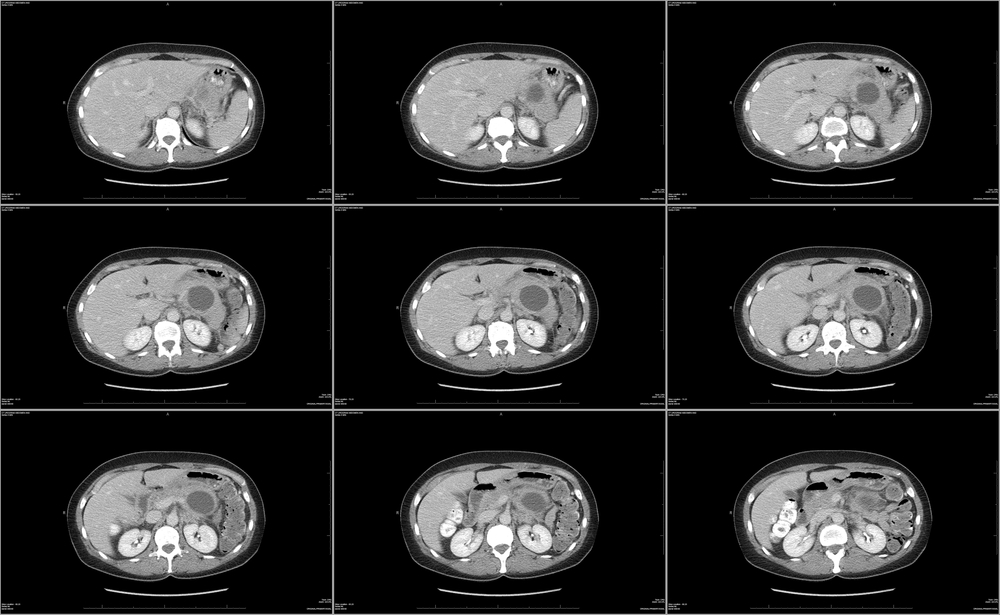

При крупном размере кисты ее иногда удается прощупать в животе в области, соответствующей проекции поджелудочной железы. Но все же чаще кисты выявляются методами современного инструментального обследования, таких как:

- КТ или МРТ (можно выявить кисты величиной от 2 см);

Эти исследования визуализируют кисты в виде жидкостных образований с четкими контурами и гомогенной структурой, позволяют оценить их число, размеры, связь с панкреатическими протоками, соотношение с находящимися рядом органами.